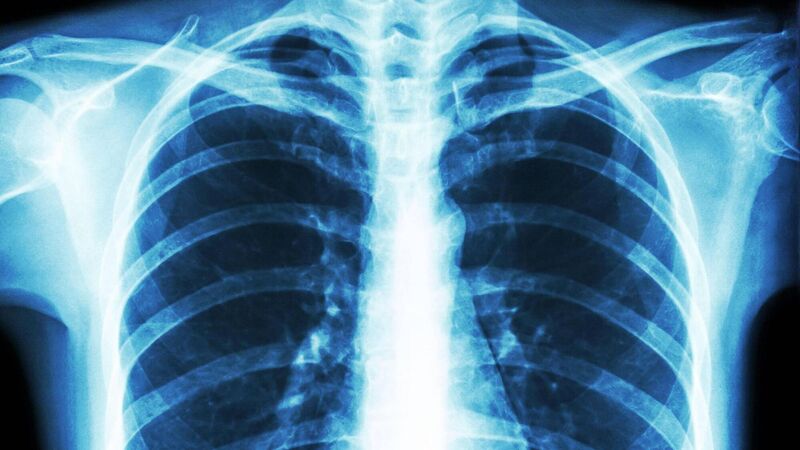

Only a 'lucky' few people with a debilitating lung condition receive specialist care

A 2021 ILFA survey of over 100 lung fibrosis and post-transplant patients found nearly half of patients received no specialty care referral.

Only a "lucky" few people suffering from a debilitating lung condition receive specialist care, an Oireachtas committee will be told on Wednesday.

The Oireachtas Health Committee will hear from the Irish Lung Fibrosis Association. It is estimated that there are 5,000 people in Ireland living with lung fibrosis, with over 1,000 new cases every year. However, data on the incidence in Ireland is lacking as there is no national registry. The prognosis for lung fibrosis patients is worse than most cancers.